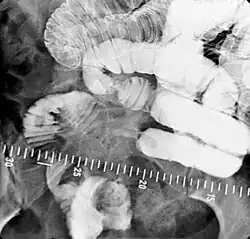

In addition to fasting for 8 hours prior to examination, a laxative may also be necessary for bowel preparation and cleansing.[12] The main aim of this study is to distend the proximal bowel through infusion of large amount of barium suspension. Otherwise, the distension of distal small bowel is generally similar with small bowel follow-through. Therefore, there is a need to pass a tube through the nose into the jejunum (nasojejunal tube) to administer large amount of contrast. This can be unpleasant to the subject, requires more staff, longer procedural time, and higher radiation dose when compared to small bowel follow-through. The indications for enteroclysis are generally similar to small bowel follow-through. Barium suspensions such as diluted E-Z Paque 70% and Baritop 100% can be used. After that, 600 ml of 0.5% methylcellulose is administered after 500 ml of 70% barium suspension is given. Bilbao-Dotter tube and Silk tube can be used to administer barium suspension. The subject should be fasted overnight, any antispasmodic drugs should be stopped one day before the examination, and Tetracaine lozenges can be used 30 minutes before the procedure to numb the throat for nasojejunal tube insertion.[13]

The filling of the small intestines can be viewed continuously using fluoroscopy, or viewed as standard radiographs taken at frequent intervals. The technique is a double-contrast procedure that allows detailed imaging of the entire small intestine. However, the procedure may take 6 hours or longer to complete and is quite uncomfortable to undergo.[23]